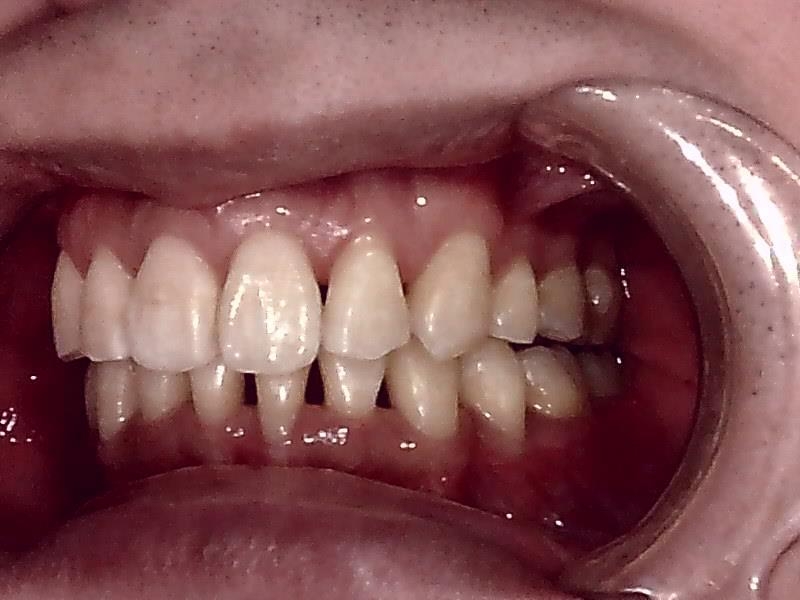

左側

右側

右側 術前の写真